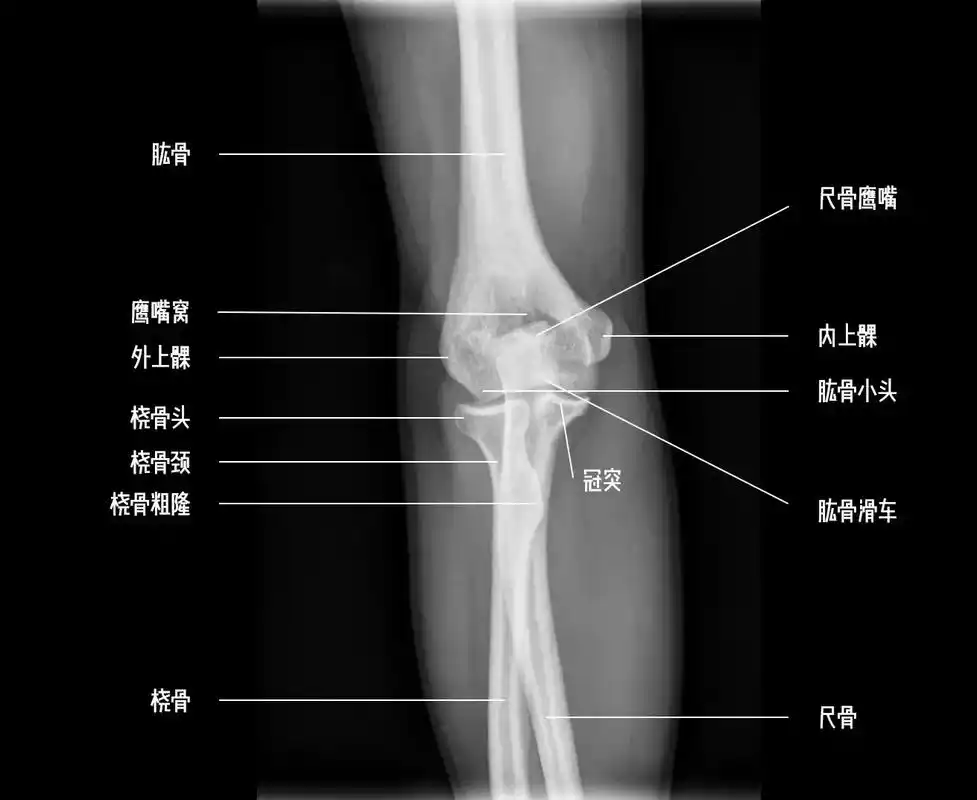

肘关节解剖.#解剖 #肘关节 #医学影像 #医学生 #医生日 - 抖音